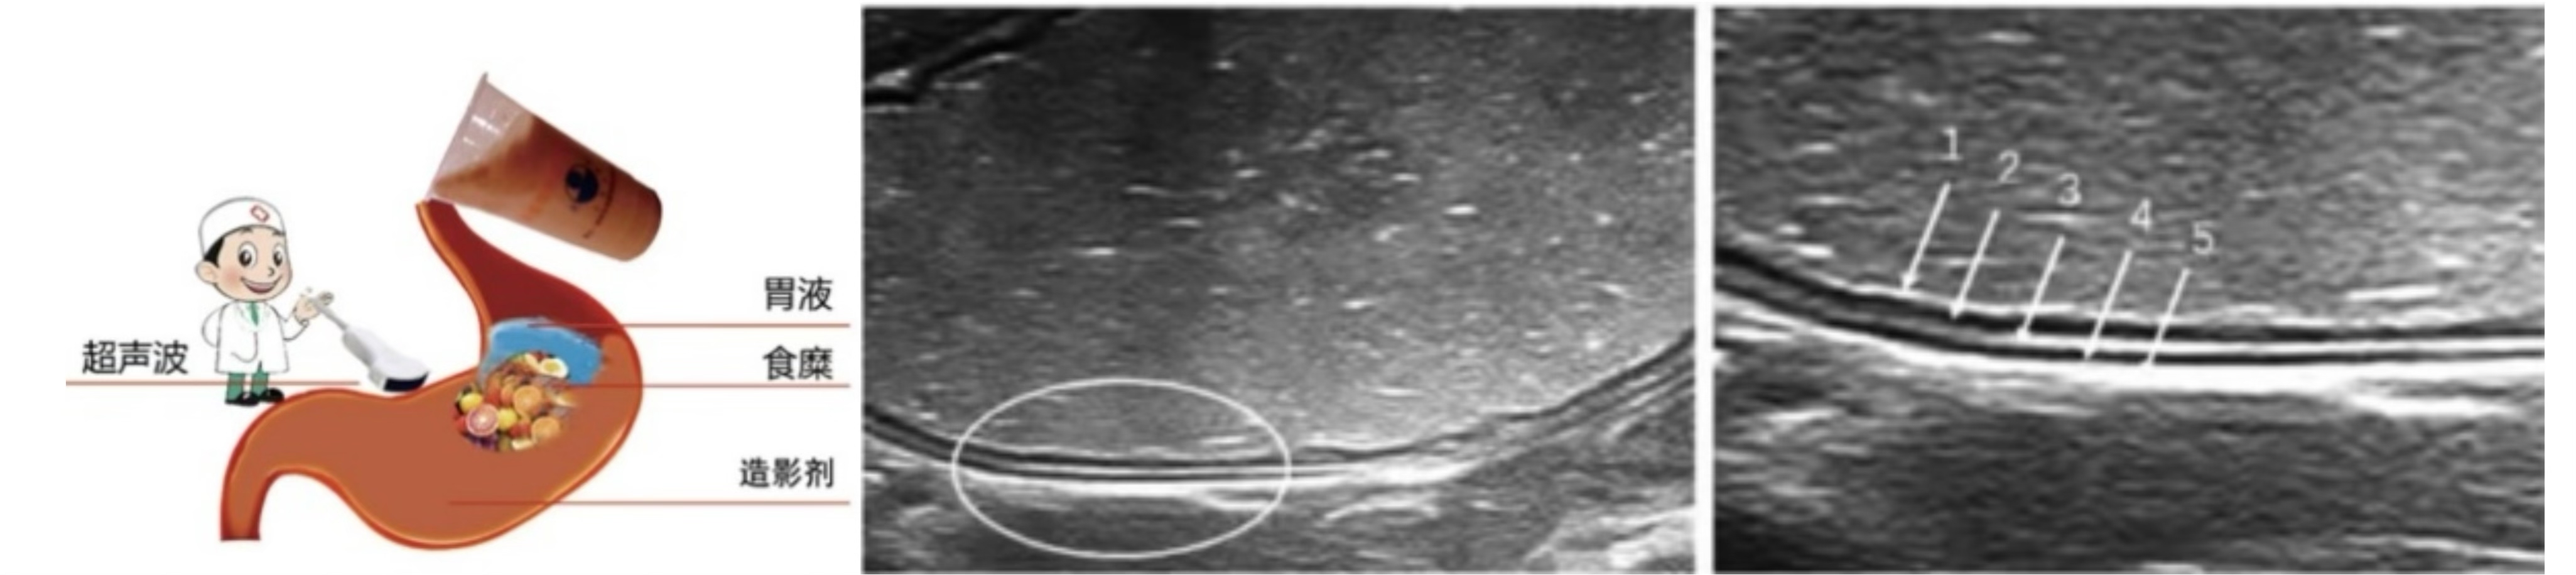

胃充盈超声检查是指患者在检查前口服超声助显剂,也就是一碗香喷喷的“养生粥”,排空胃腔内气体使胃腔充盈,在胃腔形成一种均匀分布的较强回声界面,可清晰地显示胃壁层次结构以及病变,同时为腹腔结构提供了一个声窗,还可以帮助观察以往难以发现的邻近脏器病变。

3.jpg

正常胃壁